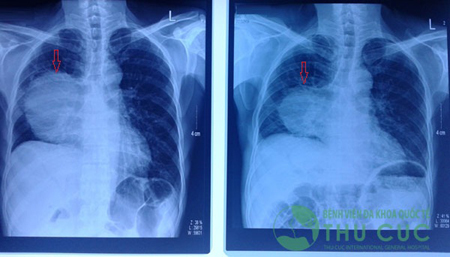

Bệnh nhân L.Q.H 51 tuổi, Thái Nguyên là một ví dụ. Ông H. bị chẩn đoán ung thư biểu mô tuyến phổi giai đoạn 4, đã từng điều trị tại một bệnh viện. Ông được xạ trị 6 lần, nhưng do bị mệt, không đủ sức khỏe nên việc điều trị phải dừng lại. Tiếp theo, ông được cho dùng thuốc TARCEVA 100mg 2 viên mỗi ngày, nhưng sau 20 ngày dùng thuốc bệnh nhân phải dừng lại do gặp nhiều tác dụng phụ của thuốc.

| Kết quả trước và sau 2 chu kỳ truyền hóa chất: khối u giảm đáng kể về kích thước, từ 11 × 10cm xuống còn 7,6 × 7,5cm. |

Khi nhập viện tại Bệnh viện Thu Cúc, ông H. bị đau nhiều vùng thượng vị, sụt hơn 10kg, vàng da, nôn mửa rất nhiều. Ông H. được tư vấn điều trị trực tiếp bởi đội ngũ bác sĩ Singapore hợp tác điều trị tại Thu Cúc. Sau khi thăm khám và nắm được tình trạng bệnh, bác sĩ Singapore cho hướng điều trị là đặt stent cho hết vàng da. Sau khi mức bilirubin giảm, người bệnh ăn uống được trở lại và sức khỏe tốt, ông H. tiếp tục được truyền hóa chất. Kết quả sau điều trị rất khả quan, mức bilirubin hạ xuống gần mức như người bình thường, khối u thu nhỏ, sức khỏe người bệnh ổn định, ăn uống được và lên cân.